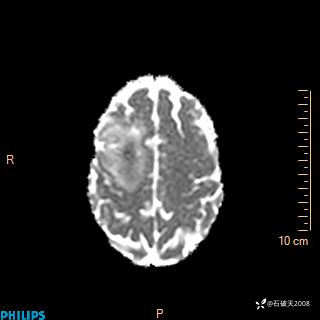

2024.2.21MR

ADC